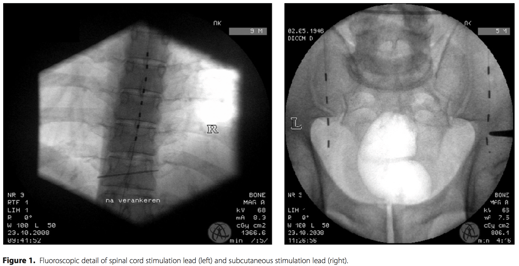

Les patients concernés présentaient des douleurs chroniques suite à une chirurgie du rachis (FBSS) et les thérapies conventionnelles ont échoué. Dans un premier temps, la SM a été mise en place afin d’évaluer la suppression de la radiculalgie et de la lombalgie. Lorsque la SM seule était insuffisante dans le traitement des douleurs lombaires, des électrodes de SSC ont été placés superficiellement au niveau lombaire, directement au centre de la zone algique. Un générateur d'impulsions a été implanté chaque fois que les patients ont mentionné une diminution des douleurs supérieure à 50% lors de cette période d'essai. L’intensité de la douleur pour les membres et les douleurs lombaires a été évaluée séparément, en utilisant une échelle visuelle analogique (EVA). La douleur et l'incapacité, évaluées sur la « Quebec Back Pain Disability Scale » (QBPDS) après 12 mois de traitement ont été comparées avec la douleur et la QBPDS initiales.

Onze patients, cinq femmes et six hommes (âge: 51 ± 8 ans), chez qui la SM seule était insuffisante dans le traitement des lombalgies ont été inclus. Dans neuf cas, les électrodes de SSC utilisées en combinaison avec la SM ont permis de traiter les radiculalgies et les lombalgies. Dans deux cas la SSC a été utilisée seule pour traiter les lombalgies. La SM a considérablement réduit la douleur de la radiculalgie après 12 mois [VAS (initial): 62 ± 14 vs VAS (+12m): 20 ± 11, p = 0,001, N = 8]. La stimulation sous cutanée a significativement réduit la lombalgie après 12 mois [VAS (Initial): 62 ± 13,0 vs VAS (12m): 32 ± 16; p = 0,0002, N = 10). La médication contre la douleur a pu être réduite de plus de 70%. La QBPDS a été améliorée, passant de 61 ± 15 à 49 ± 12 (p = 0,046, N = 10)]. En outre, deux patients ont pu retourner au travail.